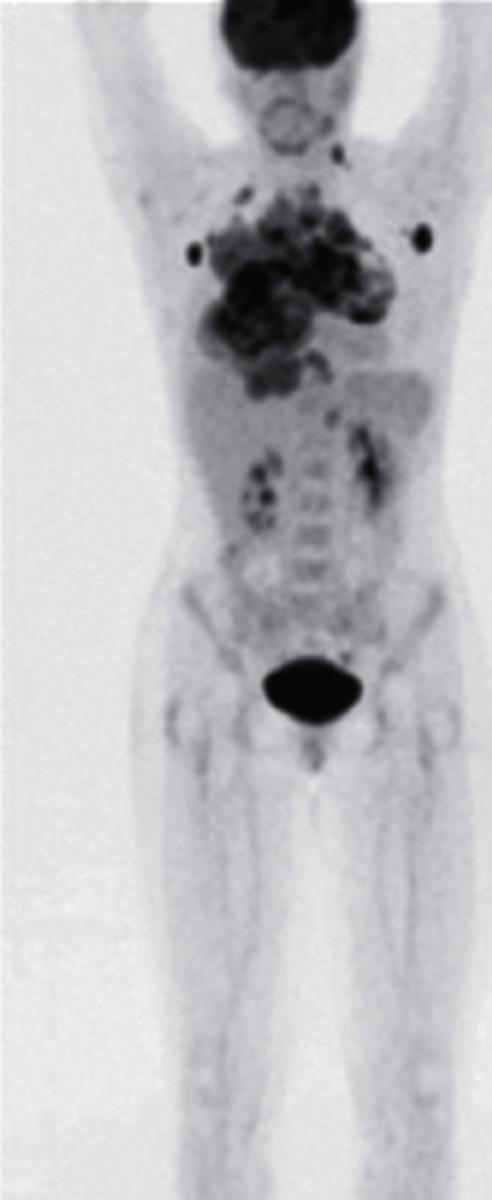

how does a PET scan occur

radiopharmaceutical is injected into the patient and the radioactive decay products are detected by gamma rays. These are capable of imaging metabolism at the molecular level.

what can a PET scan view

-quantification of blood flow and perfusion

-anatomical mapping of brain function

-study diseases such as dementia

-metabolic activity of tumors

PET scan

what type of imaging study is this?

a. Bone Scan

b. CT scan

c. PET scan

d. MRI